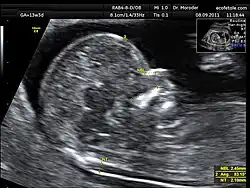

Nekplooimeting

De nekplooimeting is een echografisch onderzoek van de foetus, tussen de 11e en 14e week van de zwangerschap, waarbij de dikte van de nekplooi wordt gemeten. De plooi die op de echo wordt gezien is niet een echte plooi in de huid maar een tijdelijke ophoping van vocht onder de huid die bij elke foetus kan worden aangetoond. Een verdikte nekplooi (meer dan 3 mm) op de echo kan duiden op een chromosoomafwijking, waarvan het syndroom van Down de meest voorkomende is. Ook kan sprake zijn van een hartafwijking. Bij de risicoinschatting op de ziekte van Down wordt de nekplooimeting samen met de uitslagen van een bloedtest (combinatietest) en de leeftijd van de moeder omgezet tot een individuele risicoinschatting. De diagnose syndroom van Down zal met verdere diagnostiek moeten worden vastgesteld.